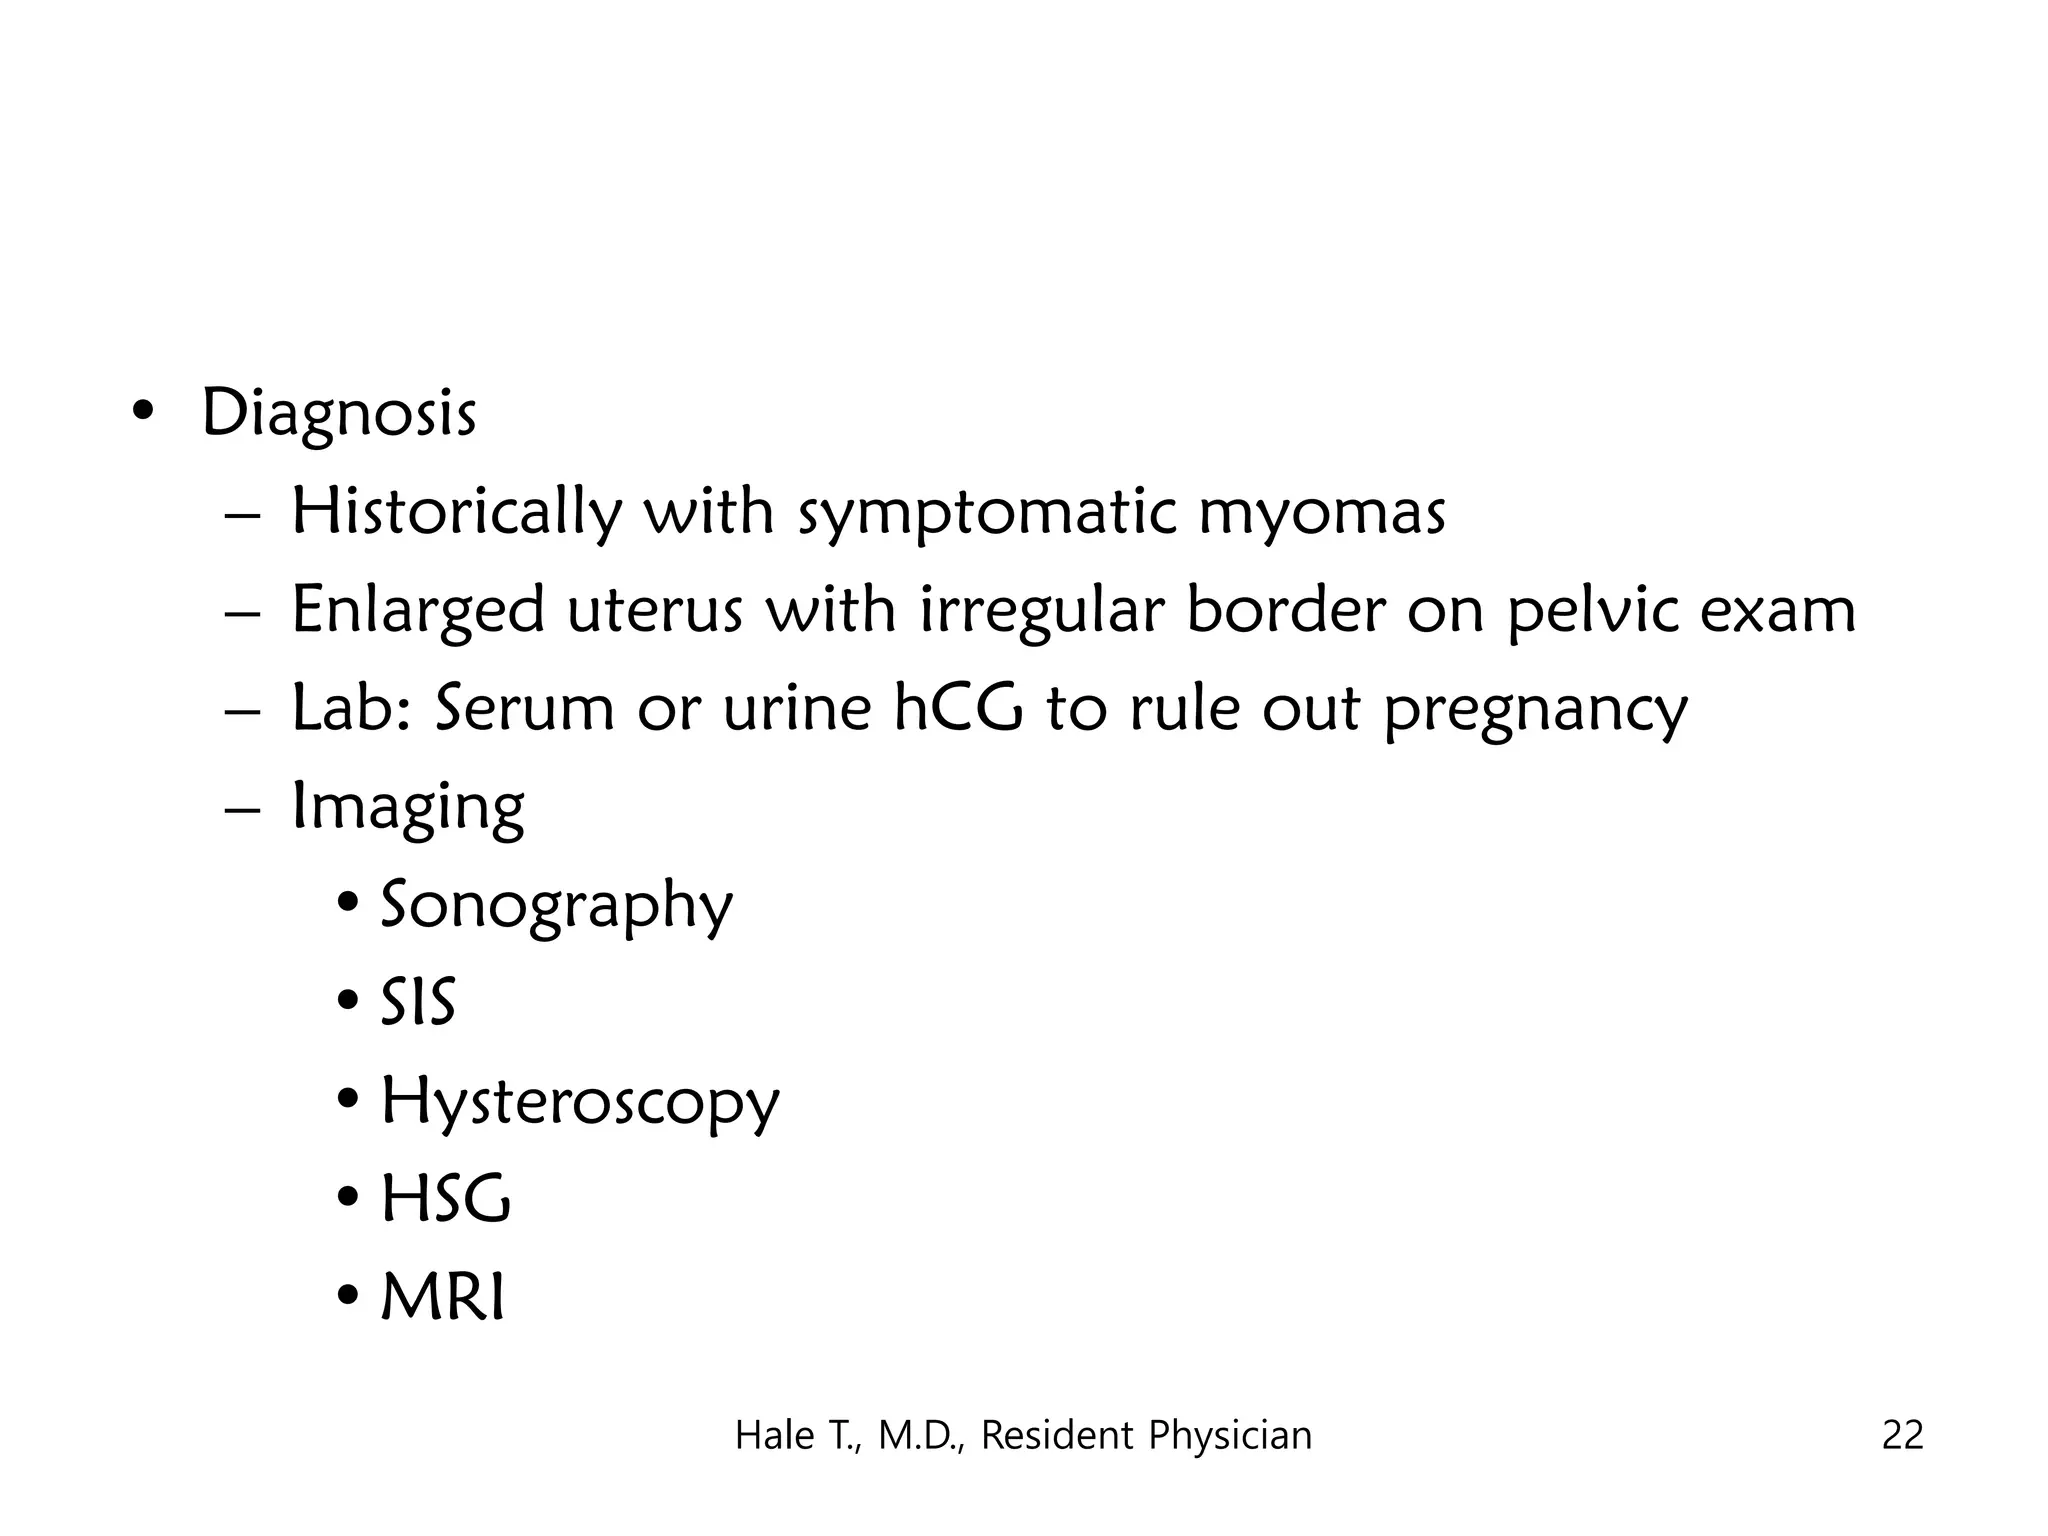

This document discusses myomas (uterine fibroids). It notes that myomas are benign smooth muscle tumors that originate in the uterus and are sensitive to estrogen and progesterone. Symptoms can include bleeding, pain, pressure, and infertility. Diagnosis is usually made through imaging like ultrasound or MRI. Treatment options include observation, drug therapy, uterine artery embolization, or surgical removal of the fibroids. The document also discusses complications that can arise if fibroids are present during pregnancy, such as pain, bleeding, preterm birth, and pregnancy loss.